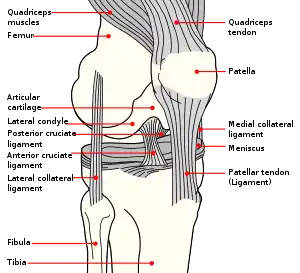

| Diagram of the right knee | |

The knee joint is formed by three bones: the femur (thighbone), the tibia (shinbone), and the patella (kneecap). These bones are held together by ligaments, which are strong bands of tissue that keep the joint stable while an individual is walking, running, jumping, etc. There are two types of ligaments in the knee: the collateral ligaments and the cruciate ligaments.

The collateral ligaments include the medial collateral ligament (along the inside of the knee) and the lateral or fibular collateral ligament (along the outside of the knee). These two ligaments function to limit sideways movement of the knee.[6]

The cruciate ligaments form an "X" inside the knee joint with the anterior cruciate ligament running from the front of the tibia to the back of the femur, and the posterior cruciate ligament running from the back of the tibia to the front of the femur. The anterior cruciate ligament prevents the tibia from sliding out in front of the femur and provides rotational stability.[6]

There are also two C-shaped structures made of cartilage called the medial meniscus and lateral meniscus that sit on top of the tibia in the knee joint and serve as cushion for the bones.[1]